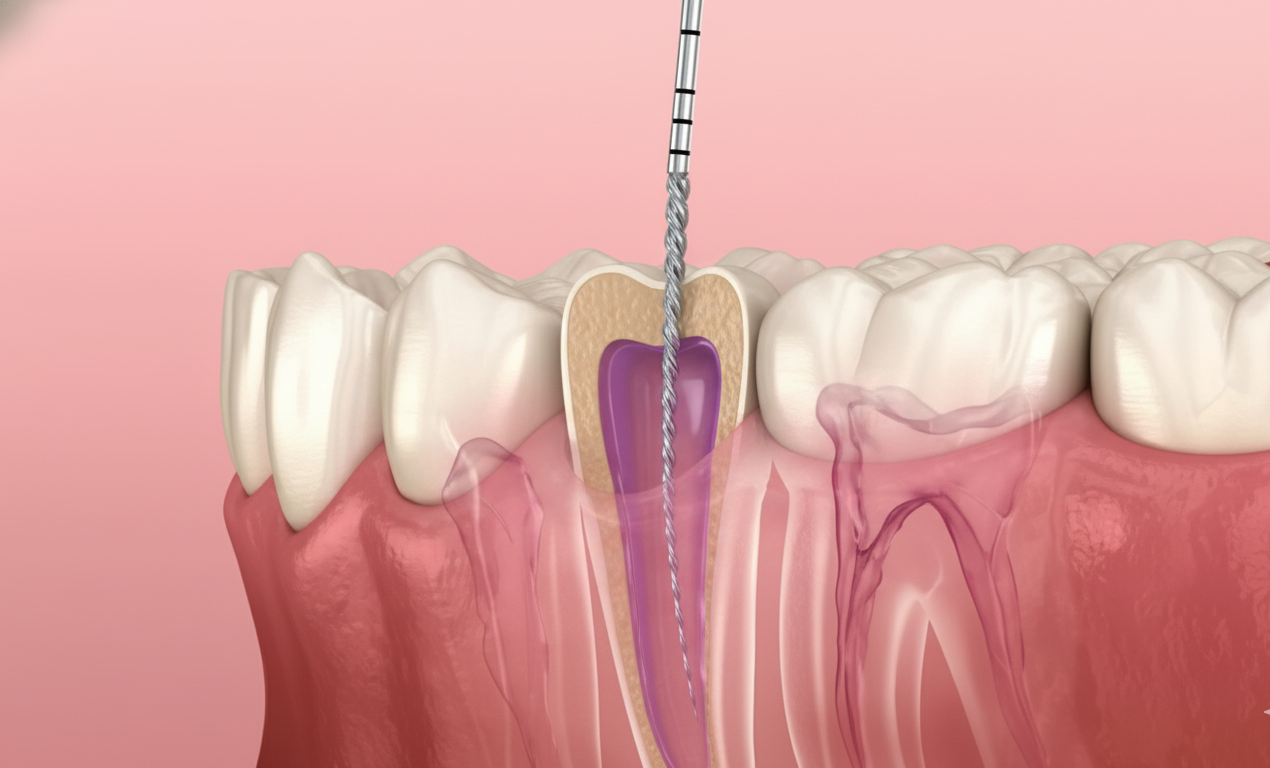

Root Canal Treatment

Removes infected pulp from inside the tooth, relieving pain and saving your natural tooth. A precise, pain-free procedure with long-term results.